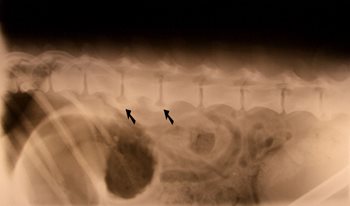

Spondylose is een aandoening van de gewrichten van de wervelkolom. Het ontstaat door instabiliteit tussen de wervels en slijtage van de tussenwervelschijven.

Tussen alle rugwervels zit een tussenwervelschijf, dit is een soort stootkussentje van kraakbeen. Deze tussenwervelschijf zorgt ervoor dat de wervels niet hard tegen elkaar kunnen botsen. Wanneer de tussenwervelschijf gaat slijten of minder flexibel wordt, gaat het lichaam dit proberen te compenseren met botwoekeringen. Dit is echter nooit zo flexibel als het kraakbeen van de tussenwervelschijf. We zien aan de onderzijde van de wervels haakvormige botnieuwvormingen. In een later stadium kunnen de haken zo groot worden dat ze contact met elkaar maken en de wervels aan elkaar vastgroeien. Bewegen wordt hierdoor lastig en pijnlijk. Spondylose is een aandoening die zich bij bijna alle dieren in de loop van hun leven ontwikkelt. Het komt over de gehele wervelkolom voor, maar bij de hond voornamelijk in het lendegebied (onderrug).

Spondylose kan worden vastgesteld door röntgenologisch onderzoek, hierop zijn de Bruggen en haken in de wervelkolom vaak duidelijk te zien.Heeft uw hond de diagnose spondylose gekregen, dan is kunt u gebruik maken van het artrose consult